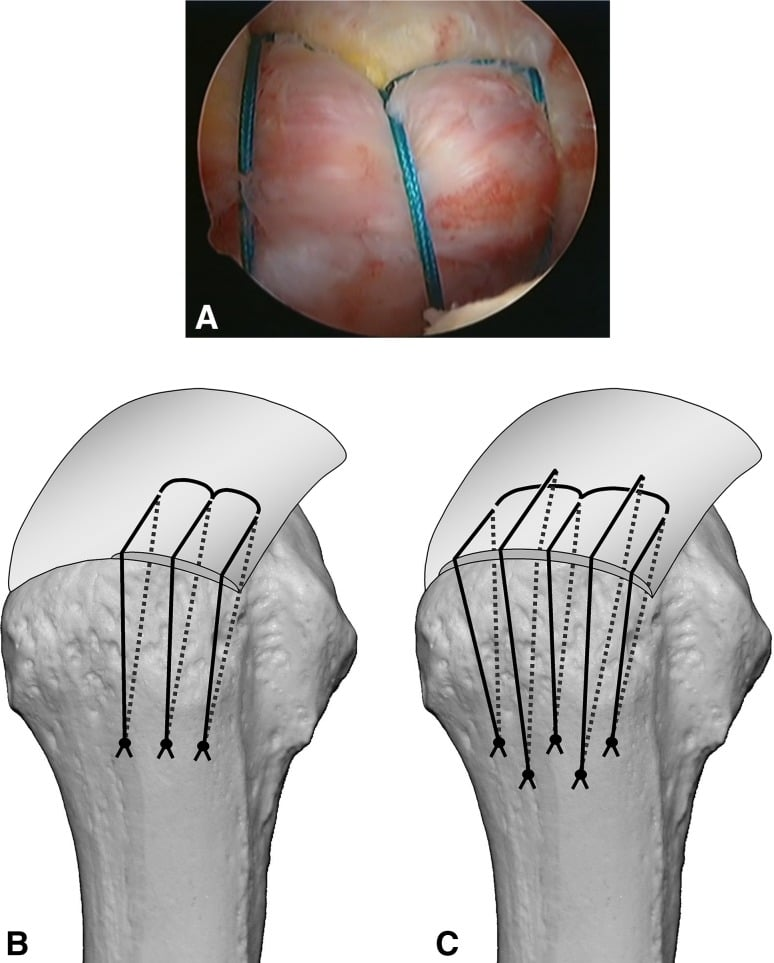

الخطاف ليس مجرد مسمار، بل هو “جهاز تثبيت” دقيق جداً (طوله لا يتعدى مليمترات)، وظيفته الأساسية هي إعادة ربط الوتر المقطوع بالعظم مرة أخرى لكي يلتئم.

- الزرع: يقوم الدكتور أحمد نبيل بزرع الخطاف داخل عظمة الكتف في المكان المخصص لالتقاء الوتر بالعظم.

- الخيوط الفائقة: يخرج من هذا الخطاف خيوط جراحية متينة جداً (أقوى من الخيوط العادية بمراحل).

- الخياطة: يتم تمرير هذه الخيوط عبر الوتر المقطوع ثم ربطها بإحكام، ليعود الوتر لمكانه الطبيعي ملتصقاً بالعظم.

- الخطاطيف “بدون عقد”: تقنية حديثة تسمح بتثبيت الوتر دون الحاجة لربط عقد جراحية، مما يقلل من سماكة مكان الإصابة.